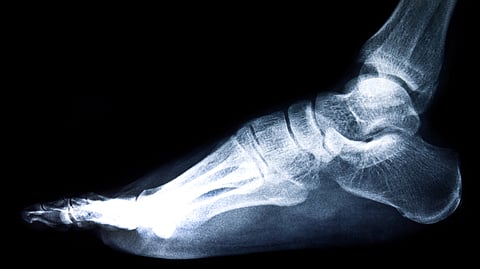

Ankle fractures are common, but when they do not heal properly, patients often face pain, stiffness, and difficulty walking. This incorrect healing, called malunion, happens when bones shift or rotate slightly during healing. Such deformities can also lead to arthritis and long-term mobility problems. Dr. Sandeep Patel, Associate Professor, Department of Orthopaedics, PGIMER, Chandigarh said to The Indian Express:

Until now, doctors had limited ways to categorise ankle malunions and plan the best treatment. In many cases, the only option for severe deformities was ankle fusion (arthrodesis), a surgery that permanently fixes the joint in one position to stop pain but also ends ankle movement.

With new surgical methods, doctors can now correct the bone alignment while keeping the joint intact. But for that, a clear system was needed to describe the deformity, understand its severity, and guide the surgery. The Patel–Dhillon Classification provides exactly that, a structured way to assess what went wrong and how it can be corrected.[1]

While the Patel–Dhillon Classification is an important step, further studies will test how well it works across different hospitals and patient groups. Researchers will also assess whether different doctors interpret the same X-rays in the same way using this system. Once validated, it could become an international reference for orthopaedic surgeons managing ankle malunions.[1]